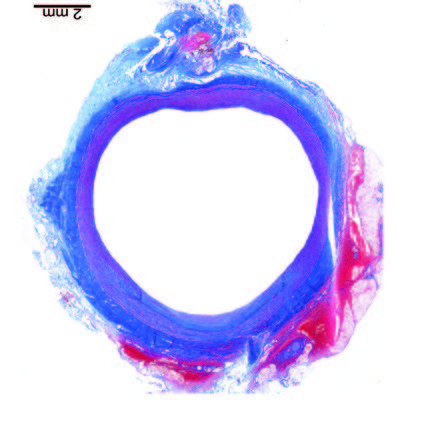

Ultra-low profile patch, rapidly endothelialised¹

Implant fully absorbed within 180 days¹

Abluminal surface matrix promotes adherence and healing¹